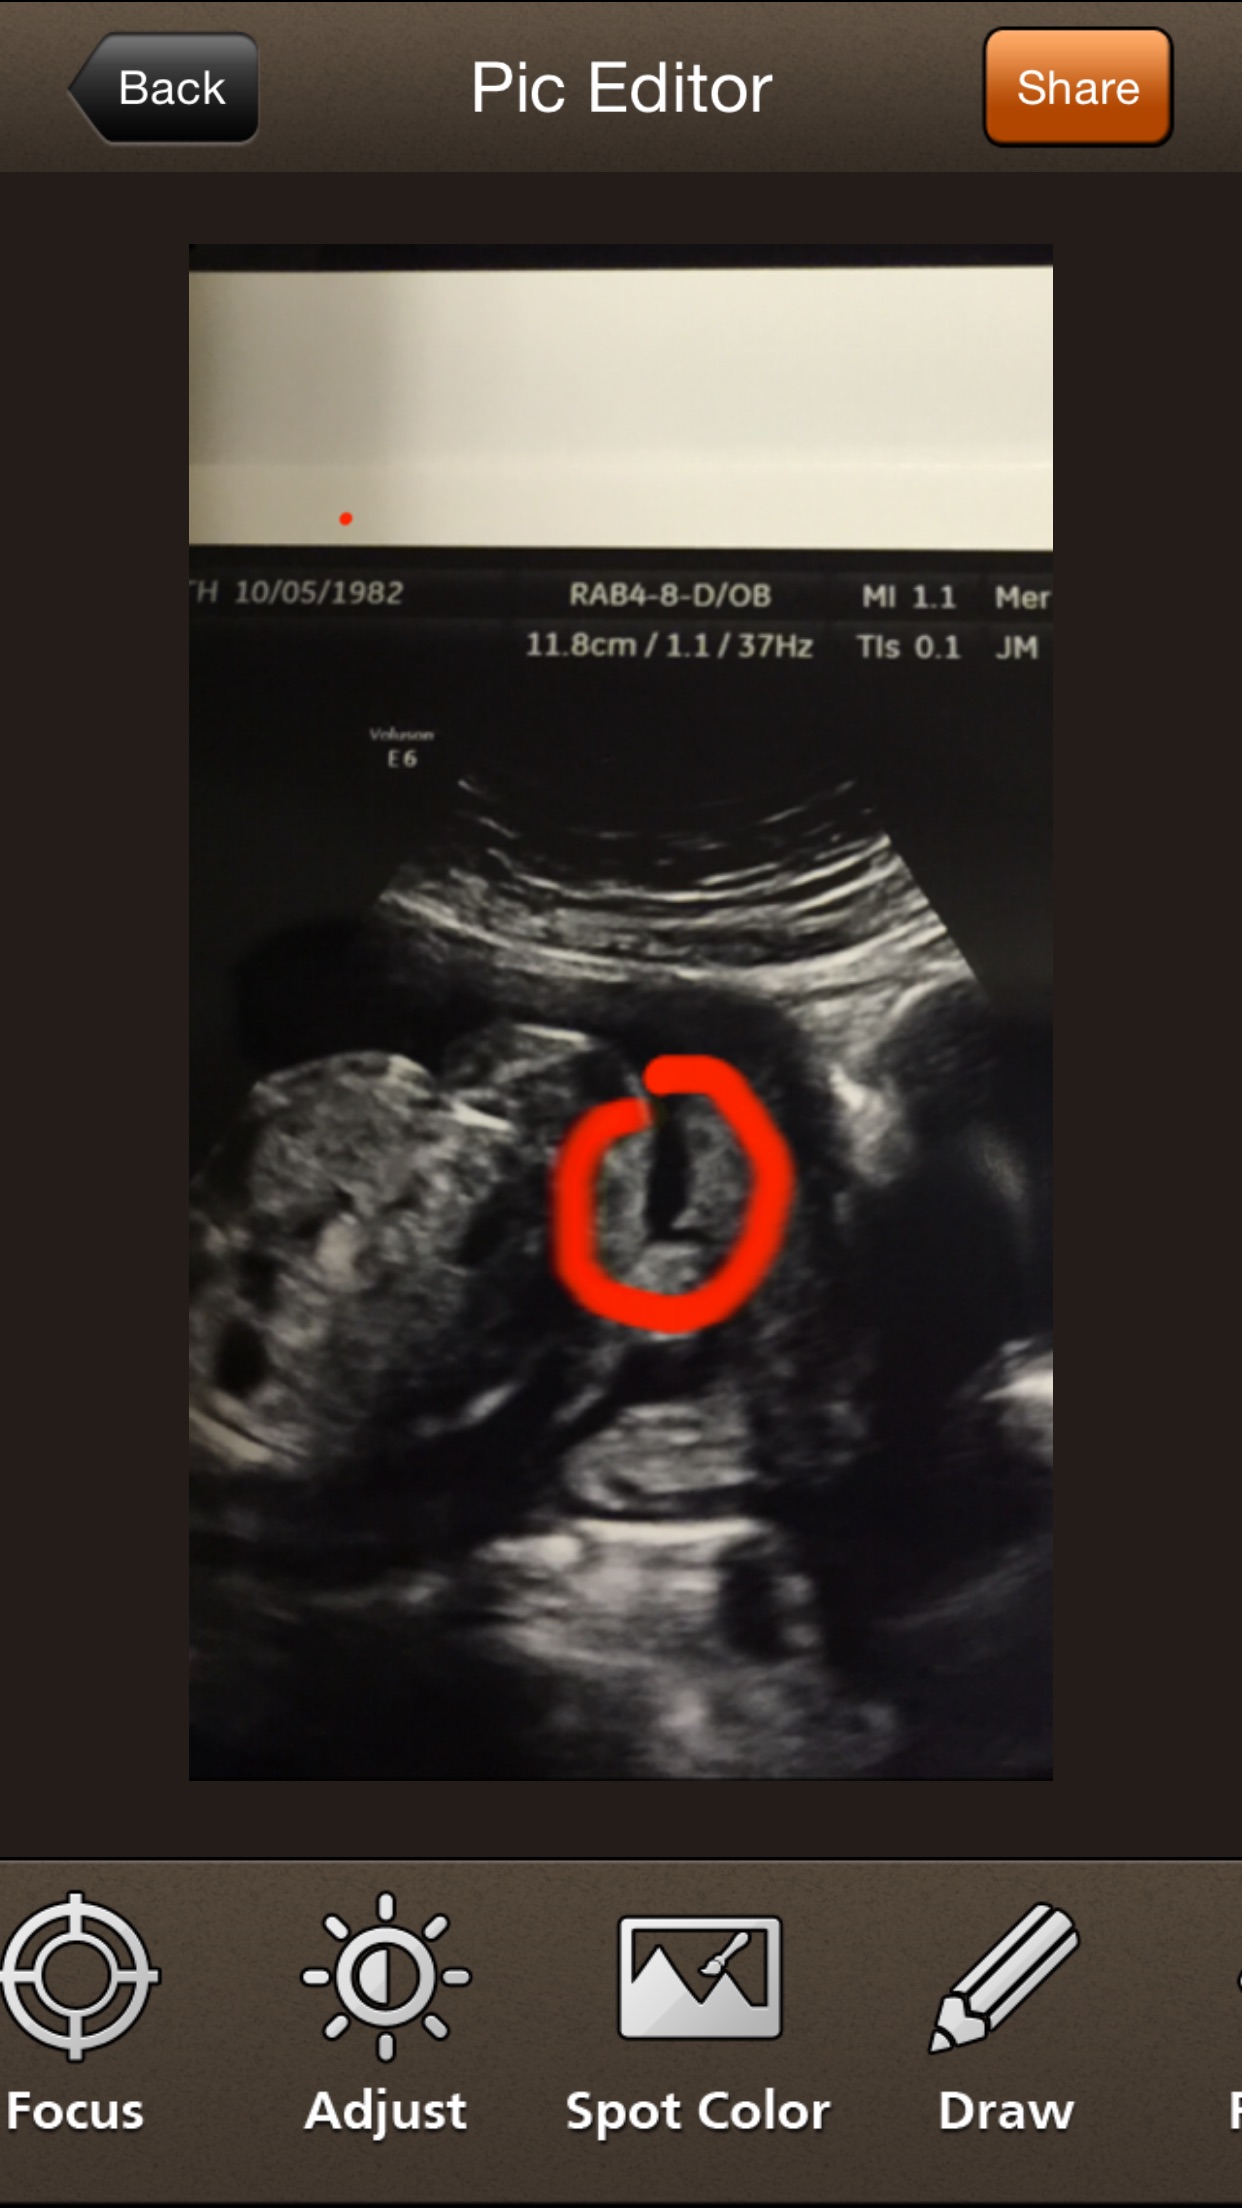

Well I had a doc appt today and tech was there and asked her what I was looking at. She said this is babies GIRLS back side sitting in her leg. I totally thought I was having a boy so a bit upset but am

Just happy baby is healthy. I am shocked maybe by some chance she is wrong...Attachment 29927Attachment 29928